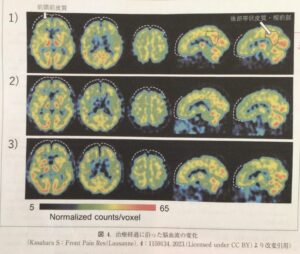

ある症例で、ADHD治療薬を投与して痛みの変化を記録したものになります。ADHD治療薬のアトモキセチン(ATX)を投与してから痛みがさらに減るといった変化がみられました。

また脳血流SPECTでも、ATXの治療経過に沿って、DMN(Default Mode Network)の楔前部の血流量が低下し、一方でCEN(Central Executive Network)の活動が上昇したため腰痛が改善したことが推察されます。